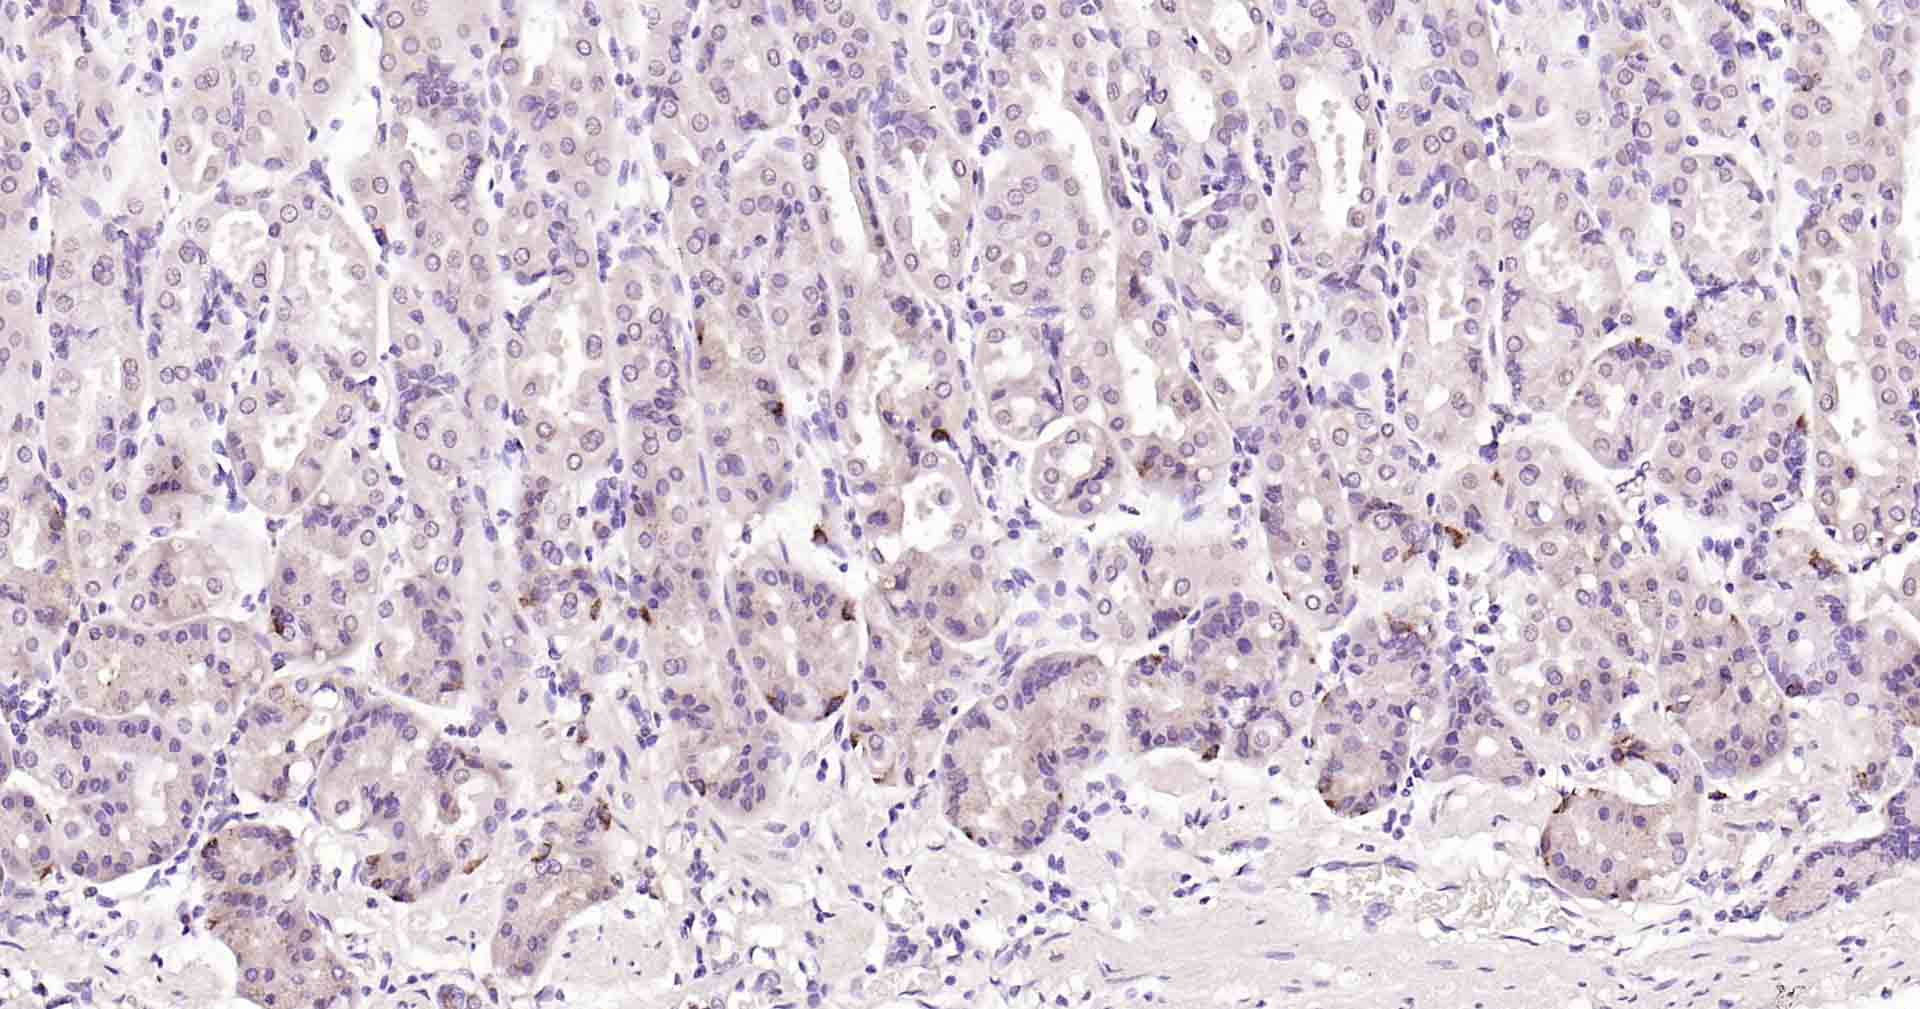

Paraformaldehyde-fixed, paraffin embedded Mouse Kidney; Antigen retrieval by boiling in sodium citrate buffer (pH6.0) for 15 min; Antibody incubation with Beclin 1 Monoclonal Antibody, Unconjugated(bsm-41365R) at 1:50 overnight at 4°C, followed by conjugation to the SP Kit (Rabbit, SP-0023) and DAB (C-0010) staining.